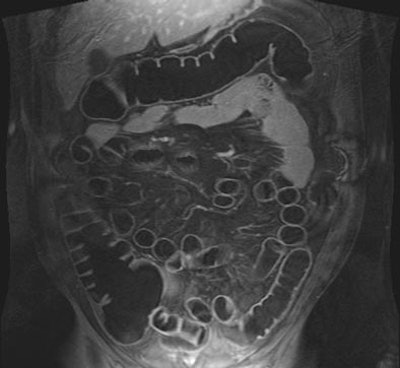

| T1-weighted GRE MR colonography images of the same patient. Top: water-filled colon following rectal enema. Bottom: study obtained on another day, following rectal insufflation with room air. Images courtesy of Dr. Thomas Lauenstein. |

Another new study by the Essen radiologists sought to determine if either air or water as a colon insufflation agent performed better in dark-lumen MRC (Journal of Magnetic Resonance Imaging, February 2004, Vol. 19:2, pp. 216-221).

The group performed dark-lumen MRC followed by conventional colonoscopy on 50 patients suspected of having colorectal pathologies, who were randomized into two groups of 25 patients undergoing either tap water or room-air insufflation prior to imaging. In addition, five healthy volunteers agreed to undergo MRC twice, once with water and once with room air, prior to the conventional exam.

MR data were acquired using a combination of two surface coils on a 1.5-tesla Magnetom Sonata scanner (Siemens Medical Solutions, Erlangen, Germany). T1-weighted 3-D gradient-echo images (96 slices, effective slice thickness 1.54 mm) were acquired in the coronal plane, and sequence parameters included TR/TE 3.1/1.1 msec, flip angle 12º, FOV 450 x 450. Then a paramagnetic contrast agent, Gd-BOPTA, was administered intravenously (0.2 mmol/kg) and the same imaging sequence was repeated after a 75-second delay.

The image-quality rating trended better with air distension (1.2 for air versus 1.3 in water among the volunteers), but the difference wasn't statistically significant. However, the use of air produced significantly better colonic distension than water (p<0.05), with a mean rating of 1.07 for air compared to 1.31 for water among the patients.

In patients or volunteers, artifacts were not a problem with either air or water distension, although there were a few artifacts related to motion or wrapping. However, there were statistically significant differences in the contrast-to-noise ratio, with a mean of 43.5 for air distension and a mean of 36.3 (p< 0.05) for water overall. Preferences among the five volunteers were inconclusive: two preferred each method, and one preferred neither.

Moreover, eight of nine lesions were detected on water-filled MRC, and no lesions were missed when air distension was used. And, they said, the use of ultrashort (0.6-second) echo times virtually eliminated the presence of susceptibility artifacts in the presence of air distension because "there is simply not time for disphasing to occur. Thus it was not surprising that image quality of air- and water-distended datasets did not reveal a statistically significant difference."

"We conclude that MRC...can be performed using either air or water as a distending agent," they wrote. Still, "slightly better CNR and improved distension of the rectum and sigmoid colon seem to favor air distension."